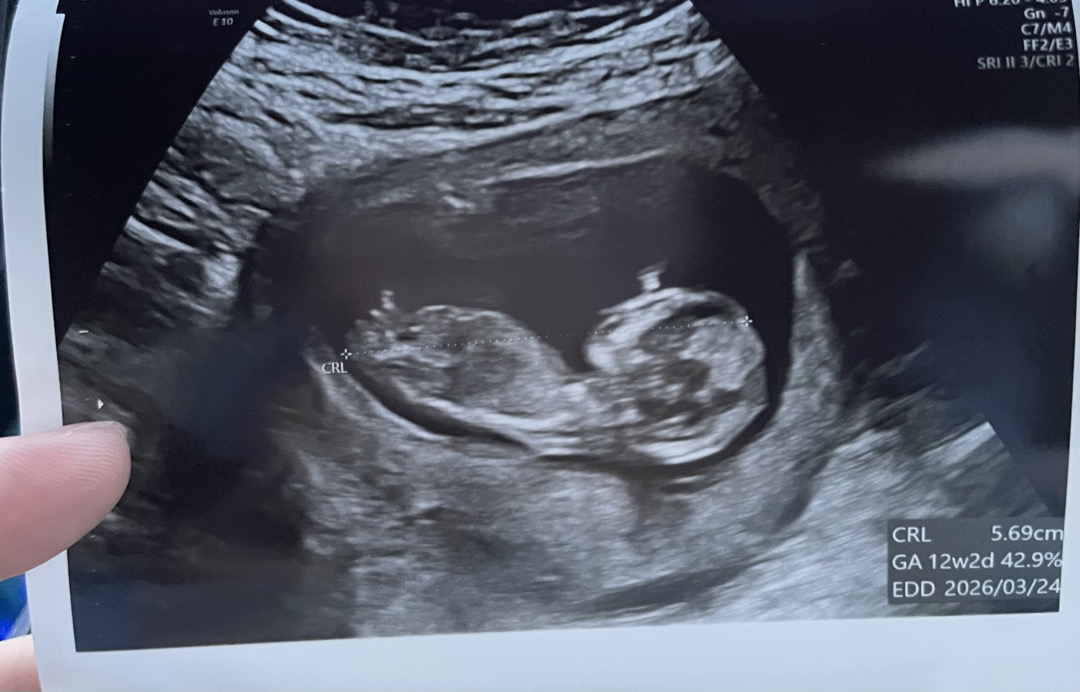

딸인거같아요

/ 성별질문

각도법 이사진에서도 보이는건가요..?

잘모르겠어요 ㅋㅋㅋ 정말 어렵네요ㅠㅠ 보이시면 투표 부탁드려용...!!

저희 첫째딸 오른쪽에 있엇어요 각도법이나 난황위치는 재미로만 보세요 ㅎㅎ